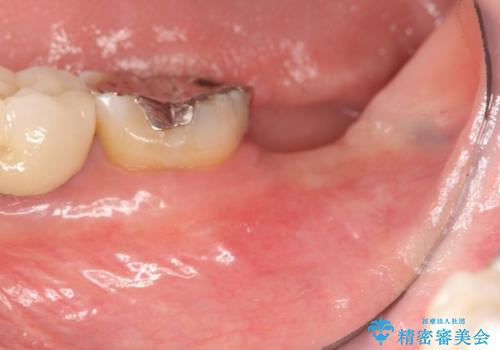

- 左下奥歯の咬合時疼痛を訴えて来院されました。

最後方臼歯周囲には大きな透過像が見られ、破折が強く疑われること抜歯が想定されることを理解していただき銀歯を除去したところ破折が認められたため抜歯を行いました。